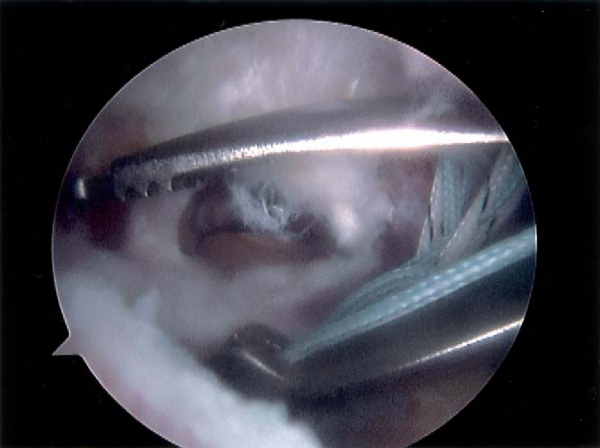

Techniques have been developed to make suture bridges that are equivalent to transosseous tunnel compression stitches. Several variations exist to form a suture bridge, and early methods made use of existing implants and instruments. The medial suture anchors are placed as previously described for a double-row technique. One suture from each anchor is placed in a horizontal mattress fashion. The second suture limbs from each anchor are then passed together just medial to the horizontal mattress sutures. This not only makes a suture bridge but also approximates a modified Mason-Allen suture construct. Either one or two lateral suture anchors may be placed just lateral to the edge of the greater tuberosity (

Fig. 17-12

). After all sutures are passed, the horizontal mattress sutures are tied. One limb from the medial compression suture and one suture from the lateral anchor are retrieved outside the lateral cannula. The suture from the medial anchor is then sewn through the lateral suture with a free needle (

Fig. 17-13

). The lateral suture, acting as a shuttle with the medial suture attached to it, is pulled through the eyelet. A second suture may be shuttled through each anchor to make a cruciate-type suture bridge, if desired, to enhance the repair (

Fig. 17-14

). After the sutures are shuttled, knot tying is performed (

Fig. 17-15

).